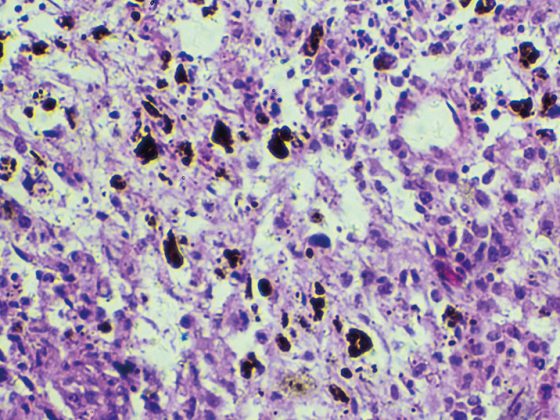

Wie Herkunft und Wohnort den CF-assoziierten Diabetes fördern